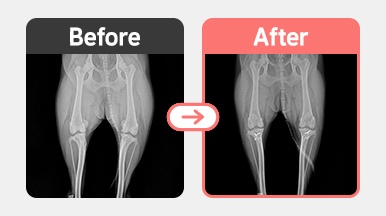

정형센터

치료후기